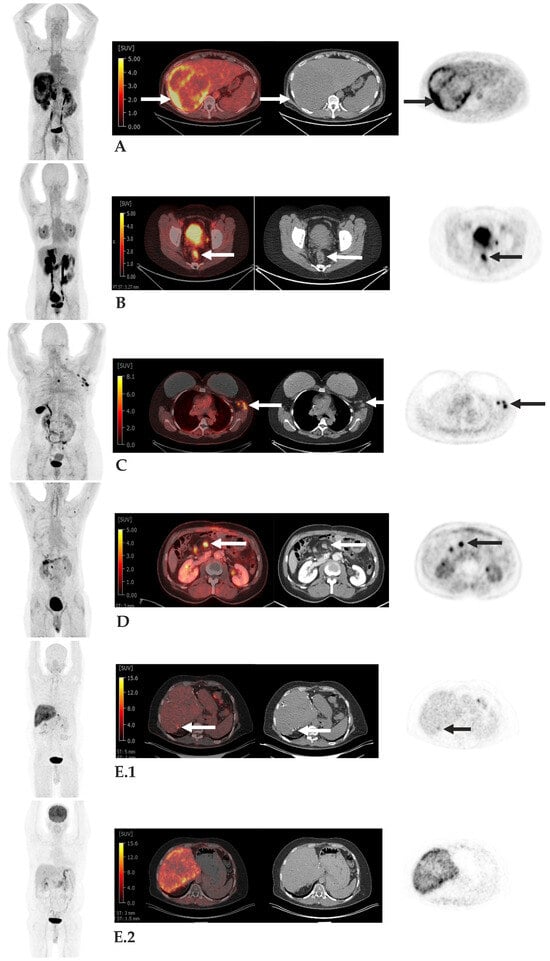

- Kratochwil, C.; Flechsig, P.; Lindner, T.; Abderrahim, L.; Altmann, A.; Mier, W.; Adeberg, S.; Rathke, H.; Röhrich, M.; Winter, H.; et al. (68)Ga-FAPI PET/CT: Tracer Uptake in 28 Different Kinds of Cancer. J. Nucl. Med. 2019, 60, 801–805. [Google Scholar] [CrossRef]

- Pang, Y.; Zhao, L.; Meng, T.; Xu, W.; Lin, Q.; Wu, H.; Zhang, J.; Chen, X.; Sun, L.; Chen, H. PET Imaging of Fibroblast Activation Protein in Various Types of Cancer Using (68)Ga-FAP-2286: Comparison with (18)F-FDG and (68)Ga-FAPI-46 in a Single-Center, Prospective Study. J. Nucl. Med. 2023, 64, 386–394. [Google Scholar] [CrossRef]

- Zhao, L.; Pang, Y.; Luo, Z.; Fu, K.; Yang, T.; Zhao, L.; Sun, L.; Wu, H.; Lin, Q.; Chen, H. Role of [(68)Ga]Ga-DOTA-FAPI-04 PET/CT in the evaluation of peritoneal carcinomatosis and comparison with [(18)F]-FDG PET/CT. Eur. J. Nucl. Med. Mol. Imaging 2021, 48, 1944–1955. [Google Scholar] [CrossRef]